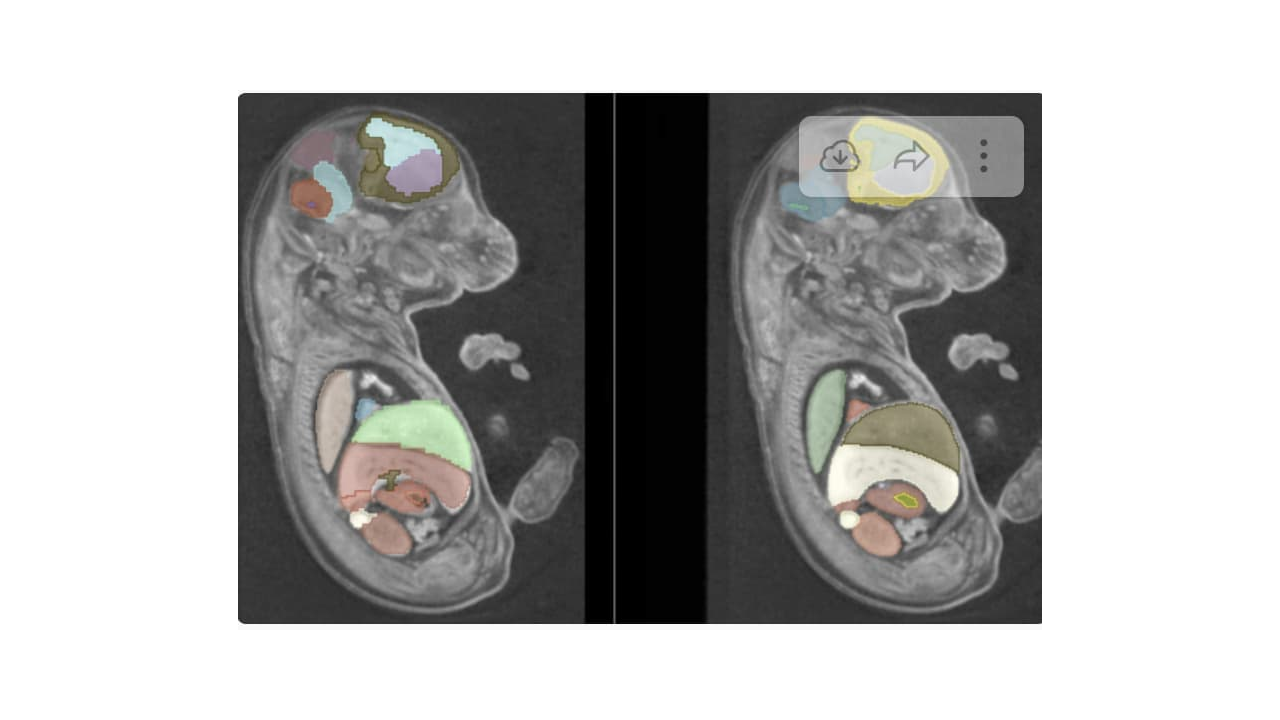

Multi-organ Segmentation in Fetal Mice

- We would like to assess whether MONAILabel can segment internal organs of fetal mice in similar quality to the deformable atlas-based registration.

- Evaluate pros and cons of both approach.

- Initial model training for mouse embryo segmentation was done a spatial resolution of 128x128x128. Training carried out to 500 epochs. While successeful, there wasn’t sufficient anatomical detail due to low spatial resolution of model.

- Edited the spatial resolution to 192x192x192 (highest we can fit on Nvidia A6000, with 48GB of RAM). Used the initial model weights, and rerun the tranining for further 100 epochs. This improved the detail considerably. We also achievied higher training dice scores on this higher resolution modes.

- Average DICE coefficient of 0.81 between inferred reference labels registered using Syn + CC. Scores similar to other state-of-the-art methods for individual organ labels.